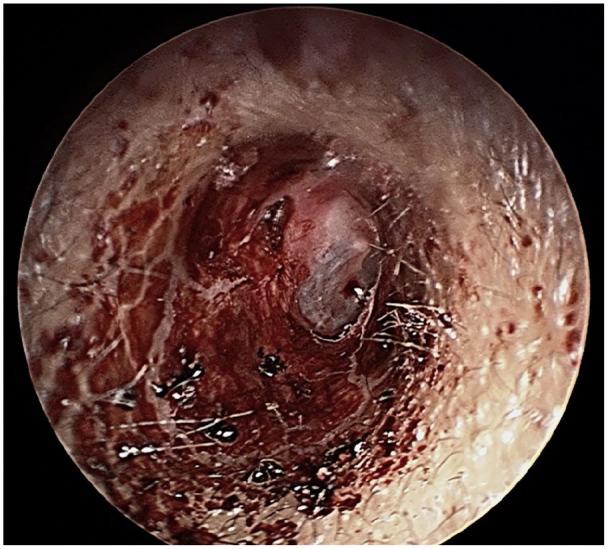

Recurrent ear bleed with profound bilateral sensorineural hearing loss: A case of Munchausen syndrome.

Factitious disorders and Munchausen syndromes present with history and physical symptoms to all specialties, and they are often extensively evaluated. Diagnosis of Munchausen syndrome is a challenge and patients often do not receive the correct diagnosis and appropriate care especially in settings where access to mental health professionals is difficult. We present a case of recurrent bleed from the right ear, bilateral profound hearing loss and jerky movement of limbs that was extensively evaluated and followed up for 4 years until a diagnosis of Munchausen syndrome was reached. This case reports the risk of harm to the patient and wastage of healthcare resources unless physicians begin to actively evaluate for factitious disorders.